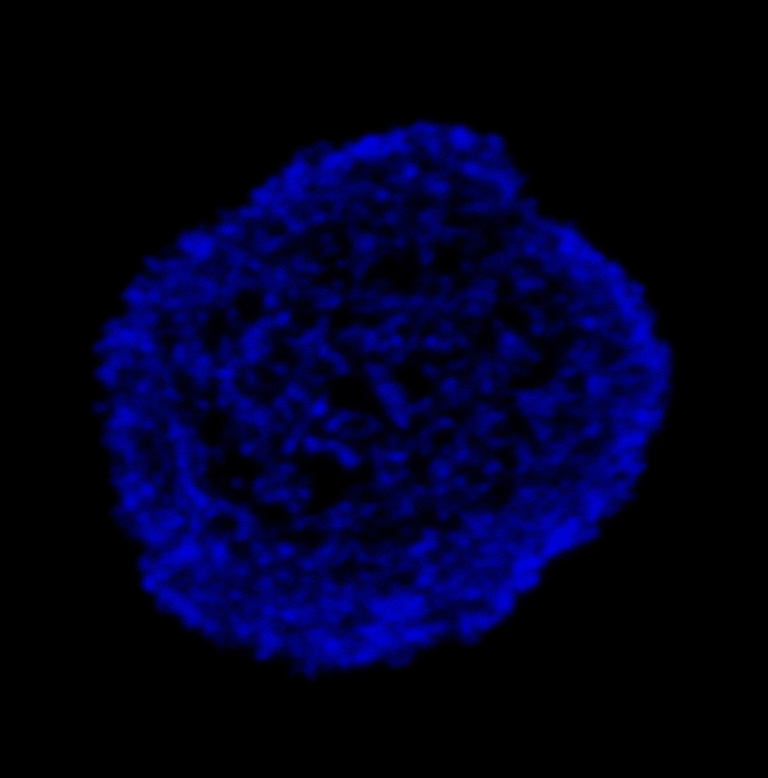

This image depicts a leukemia cell that is stained using immunofluorescence. The blue staining is DAPI, which intercalates DNA. The green color represents labeled replication forks. My thesis project attempts to elucidate how perturbed replication forks induce epigenetic reprogramming in leukemia. In leukemia, replication stress can lead to broad epigenetic changes and alterations in cell state. I hope to contribute to a better understanding of how this phenomenon occurs, which could eventually lead to the discovery of new therapeutic targets for blood cancers.